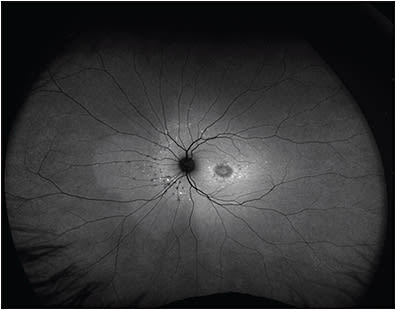

The peripheral retina manifests a variety of vitreoretinal disorders, including retinal vascular diseases, peripheral retinal degenerations, uveitis, retinal or choroidal tumors, and hereditary retinal dystrophies, among others.1,2 The gold standard for evaluation of the retinal periphery is a dilated fundus exam (DFE) with scleral depression performed by an experienced retina specialist. Recent technological advances in widefield (WF) and ultrawidefield (UWF) cameras have enabled unparalleled imaging of the retinal periphery, in contrast to older technology that captured about 30° to 50° of the posterior pole (Figure 1) and into the midperiphery with sweep views.3

There are 3 currently available noncontact-based imaging systems. The Clarus 500 is a slit-scanning ophthalmoscope that uses broad-line fundus imaging — a combination of SLO and traditional fundus photography — to capture WF and fundus autofluorescence images.12 Its field of view is 133° in a single image, up to 200° for 2 images, or up to 267° for a montage of 6 images. It is most notable for its ability to take true-color images using 3 wide-spectrum light-emitting diodes to capture more accurate coloration of the fundus and reduce optic nerve head bleaching (Figure 2). It has multimodal imaging capabilities for FAF, and the Clarus 700 can also capture FFA images.